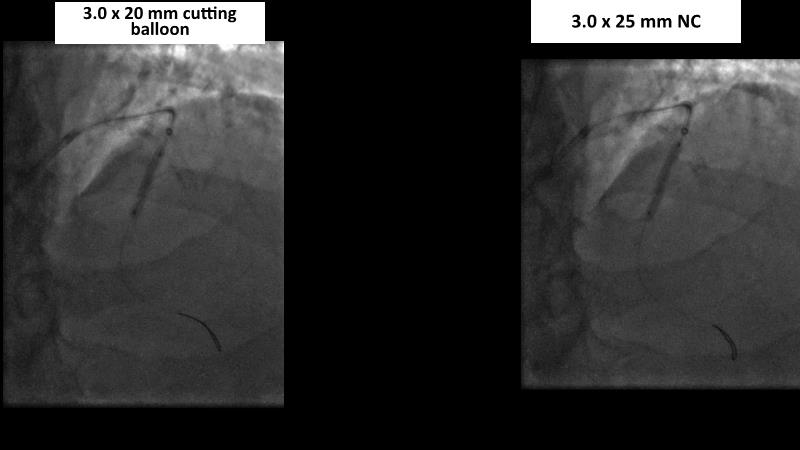

Watch this session to gain case-based insights on using DCBs in complex settings. Learn valuable tips and tricks for optimal DCB application, including the best timing and situations for their use. Discover how to effectively implement a hybrid strategy that combines DES and DCB when needed.

- To get a case based experience on how to use a DCB in complex settings

- To learn about tips and tricks on how and when to use a DCB: the ideal time and situation of DCB application in various complexities

- To utilise the hybrid strategy approach Combining DES and DCB when the situation demands